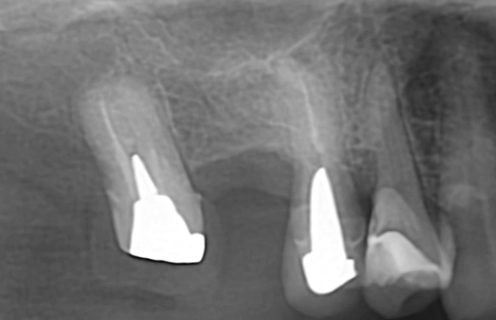

術前レントゲン・CT評価

右上欠損部では、上顎洞底までの距離が短く、埋入に必要な垂直的骨量が限られていました。

安全性と長期安定性を確保するため、骨条件に合わせた術式選択が必要と判断しました。